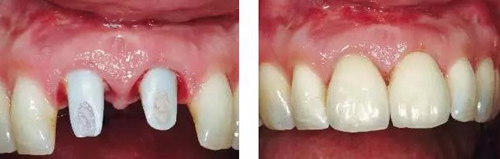

圖10、剛植入種植體當(dāng)天的情況(左)和植入種植體1年時(shí)的情況(右)。

圖11、牙冠戴入1個(gè)月以后。軟組織外形良好,形成了良好的弧線形牙齦形態(tài)而沒(méi)有瘢痕。保持了原有的色素沉著的顏色和形狀。

圖12、種植術(shù)后1年顯示良好的美學(xué)效果。